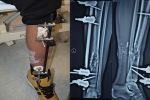

Військовий воював у 28-й механізованій бригаді. Йому - 34 роки, з яких останні два - це виснажлива боротьба за життя. Кома, більш ніж два десятки операцій, шпиталі Дніпра і Києва, півроку лікування в Німеччині.

"У Німеччині мені виростили кістку, 18 сантиметрів кістки. А з суглобом вони нічого не могли зробити", - розповідає Роман.

Плечового суглоба у чоловіка немає. Його чекала або ампутація, або жорстка фіксація без шансу хоч колись порухати і відчути свою праву руку. "Йому пропонували той шматок плеча, що лишився, просто взяти та з лопаткою зростити…У нього лопатка, наче крило стирчало б", - каже хірург Володимир Оксимець.

Минулого вівторка Роману зробили підготовчу операцію, та попереду ще 2-3. Медики планують відростити необхідні кісткові фрагменти і наново скласти плечовий суглоб. Процес тривалий, болючий і недешевий, але пацієнт уже широко усміхається. Він не має сумнівів - ще трішки й зможе обійняти дружину, дочку й сина обома руками.